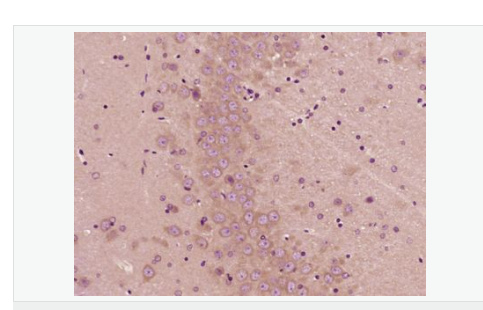

| 產(chǎn)品介紹 | PBR (Peripheral type Benzodiazepine Receptor) is a ubiquitous protein (18 kDa) found in most steroidogenic tissues. It is located primarily in the outer mitochondrial membrane of steroid producing tissues and is found in association with a 34 kDa voltage dependent anion channel protein (VDAC). PBR interacts with some benzodiazepines and has different affinities than its endogenous counterpart. PBR appears to be a key factor in the transport of cholesterol from the outer to the inner mitochondrial membrane to permit the initiation of steroid hormone synthesis. It is thought to be part of the mitochondrial permeability transition pore (PT) and to be involved in apoptosis. It is speculated that patients with congenital lipoid adrenal hyperplasia, who cannot make any steroids, might have a genetic lesion in BZRP. A short form, PBRS is also expressed in the same tissues, but at a level about ten times that of PBR. Function: Responsible for the manifestation of peripheral-type benzodiazepine recognition sites and is most likely to comprise binding domains for benzodiazepines and isoquinoline carboxamides. May play a role in the transport of porphyrins and heme. Plays a role in the transport of cholesterol across mitochondrial membranes in steroidogenic cells. Subcellular Location: Mitochondrion membrane. Tissue Specificity: Found in many tissue types. Expressed at the highest levels under normal conditions in tissues that synthesize steroids. Similarity: Belongs to the TspO/BZRP family. SWISS: B1AH88 Gene ID: 706 Database links: Entrez Gene: 706 Human Entrez Gene: 12257 Mouse Omim: 109610 Human SwissProt: B1AH88 Human SwissProt: P30536 Human SwissProt: P50637 Mouse Unigene: 202 Human Unigene: 1508 Mouse Important Note: This product as supplied is intended for research use only, not for use in human, therapeutic or diagnostic applications. 地西泮結合抑制因子; DBI能拮抗安定物質(zhì):diazepam與腦突觸膜相結合 ,故稱(chēng)之為安定結合抑制蛋白(DBI),地西泮結合抑制因子(diazepam binding inhibitor,DBI)具有抑制由葡萄糖誘導的胰島素分泌、促進(jìn)膽固醇跨線(xiàn)粒體膜轉運和調節脂肪酸合成與代謝等多種生理功能。 |